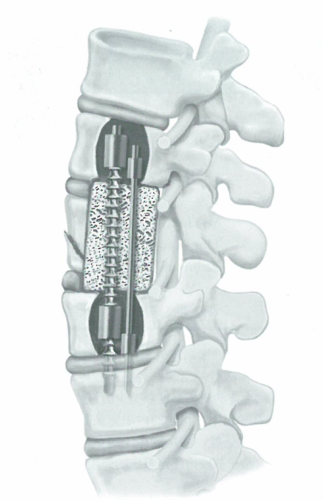

肿瘤切除前路内固定应用,脊柱内固定系统进行胸腰段的前柱重建,可以增加融合率,并提供即刻的稳定性。赴美就医机构爱诺美康了解到,至早将前路内固定系统应用于胸腰段的是Dwyer及其同事,用线缆和螺钉系统矫正脊柱侧弯。Zielke及其同事应用3.2mm粗的单个螺棒及螺帽取代线缆,改良了Dwyer系统。Kostuik曾经报道应用Dwyer-Hall椎体板和Harrington撑开棒(前路Kostuik-Harrington系统)进行前路脊柱固定,治疗脊柱骨折(图1)。

图1 前路Kostuik-Harrington系统。